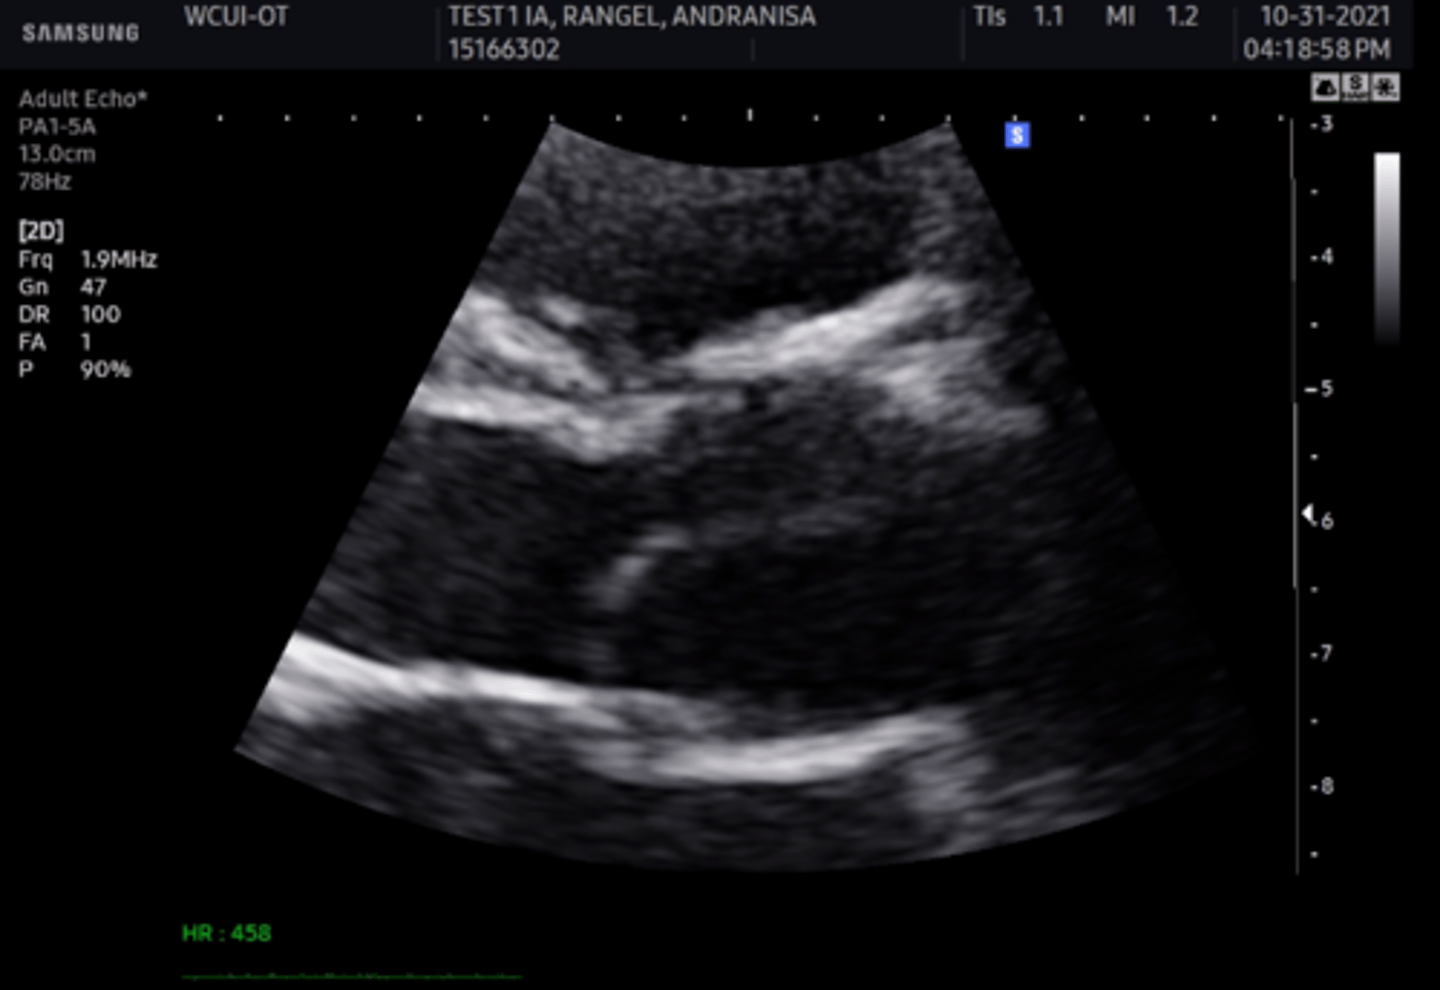

anterior mitral valve leaflet

left leaflet

posterior mitral valve leaflet

right leaflet

posterior mitral valve leaflet

left leaflet

anterior mitral valve leaflet

right leaflet